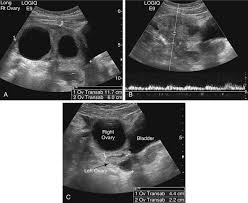

Both ovariesdemonstrate a normal sonographic appearance. Beyond this, any pouch or sac filled with fluid or other tissue that formed on the ovary is also an ovarian cyst. 3 may 2019 21:52 in response to mumoftwo34. The right ovary measures 2.5 x 2.2 x 1.7 cm and contains a 2.2 cm simple cyst. Symptoms of ovarian torsion include nausea, vomiting, and pain in the lower belly or pelvis. Is a 3.4 cm ovarian cyst big? These grow to about 2.5 cm, or one inch, and then when the woman ovulates or releases the egg the cyst drains and is gone. Ovarian cancer and cysts have similar symptoms and signs, for example, pain during intercourse, pelvic pain, and urinary problems. Using a laparoscope — a slim, lighted instrument inserted into your abdomen through a small incision — your doctor can see your ovaries and remove the ovarian cyst. In the month of june 08, both my ovaries were normal without any sign of cyst. Ovaries are actively making hormones and ripening eggs from when the period first starts until when she goes through menopause. Complex ovarian cysts are very rare but they can cause many serious problems and complications, including emotional isolation because of the condition. Ovulation happens when these cysts are around 2 to 3 cm in size.

The left ovary measures 2.1 x 2.0 x 1.5 cm. Most functional cysts are 2 to 5 centimeters (cm) (about 3/4 of an inch to 2 inches) in size. But if the ultrasound shows that the cyst is still growing then it requires a more serious approach. Is a 3.4 cm ovarian cyst big? I was diagnosed as having a 9.1 cm ovarian cyst in my right ovary two days ago.

Around ovulation, the follicle measures around 2 cm, so this is a little bigger. Report was given to my dr who called me with the results. As far as cysts go, it is not that large and still on the small side. In general, ovarian cysts can range from under 0.5 inches (1.27 cm) to more than 12 inches (30.48 cm). In a small minority of cases, cysts can be cancerous. If you're having abdominal pain or discomfort that doesn't seem quite normal, it's possible that you have an ovarian cyst. Ovarian cysts in the neonate are exceedingly rare. I am due to have an operation, well actually i was supposed to have it last monday but it got cancelled after waiting 7 hours and im still awaiting a date.

Complex cysts are more likely to need treatment than simple cysts. He said according to the report, there no urgency, meaning. A normal ovary is about 2 x 3 cm (almond sized). It is estimated that 5% of all abdominal masses in the first month of life are ovarian cysts. A follicular ovarian cyst, if the egg is not ejected and the amount of fluid continues to increase, can reach sizes of up to 10 cm.